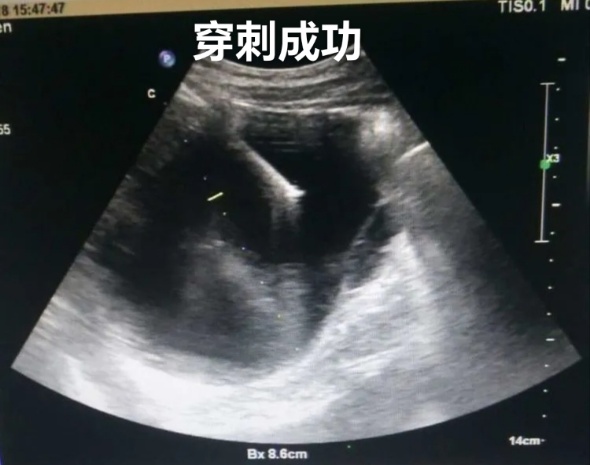

3、超声引导下置管引流,胸腹水穿刺及置管引流、心包积液穿刺置管引流、脓肿穿刺置管引流。

肝囊肿经皮超声引导性介入治疗